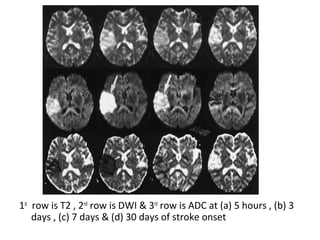

-In the acute phase T2WI will

be normal but in time the

infarcted area will become

hyperintense. The

hyperintensity on T2WI

reaches its maximum

between 7 and 30 days after

this it starts to fade

DWI is already positive in the

acute phase and then

becomes more bright with a

maximum at 7 days , DWI in

brain infarction will be

positive for approximately for

3 weeks after onset (in spinal

cord infarction DWI is only

positive for one week)

-ADC will be of low signal

intensity with a maximum at

24 hours and then will

increase in signal intensity

and finally becomes bright in

the chronic stage

1st

row is T2 , 2nd

row is DWI & 3rd

row is ADC at (a) 5 hours , (b) 3

days , (c) 7 days & (d) 30 days of stroke onset